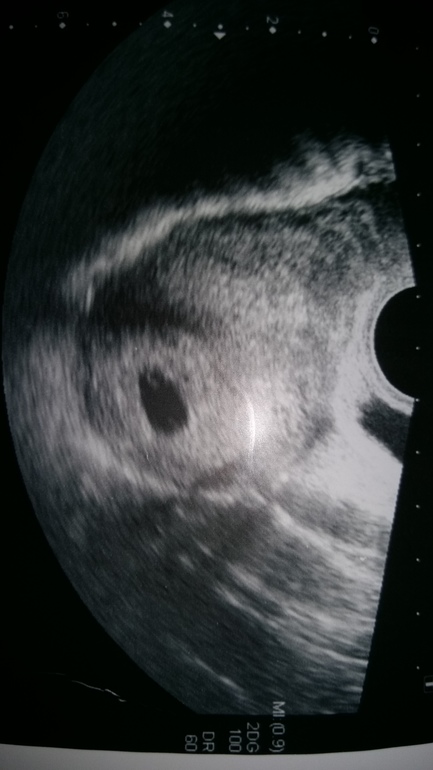

В общем по УЗИ все хорошо у нас. Угрозы нет. Все в норме. Срок поставила 9-10 нед. По мес. вчера было 10.4. По овуляции на недельку меньше-9.4.

И вот такие наши параметры:

Плодное яйцо-59мм.

Хорион кольцевидный по задней стенке, толщиной 9мм.

КТР-26ММ.